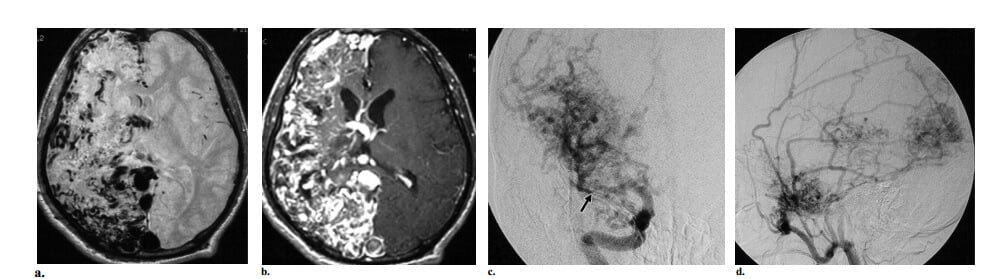

Nếu có một nidus, có thể gặp hai phân nhóm mạng lưới mạch máu bất thường. Kiểu thông thường là nidus kiểu hình cầu hay kiểu đặc, gồm các mạch máu bất thường mà không có bất kỳ một nhu mô não bình thường nào xen vào (hình 2, 3). Kiểu thứ hai hiếm gặp hơn, còn gọi là nidus kiểu tăng sinh hay lan tỏa, trong đó nhu mô não bình thường xen vào khắp đám rối mạch máu (hình 4). Nếu có dấu hiệu này, bệnh mạch máu tăng sinh hoặc hội chứng phân đoạn động-tĩnh mạch não-mặt (CAMS) cần phải đưa vào trong chẩn đoán phân biệt và có thể phân biệt với AVM não thực sự dựa vào sự vắng mặt của dẫn lưu tĩnh mạch sớm thấy trong bệnh mạch máu tăng sinh, vị trí kinh điển và đi kèm AVM mặt gặp trong CAMS.

Hình 2: AVM não kiểu nông kinh điển ở bệnh nhân nam 18 tuổi có máu tụ vùng đính trái. (a) Axial cản quang cho thấy một đám rối cấu trúc dạng ống bắt quang mạnh nhúng trong thùy đính trái, một dấu hiệu hợp với nidus. Ghi nhận tăng đậm độ biểu hiện xuất huyết trong não thất. (b) Hình ảnh hướng cường độ tối đa (MIP) (nhì từ đáy) từ dữ liệu chụp mạch CT cho thấy lớn động mạch não giữa trái (so với bên phải), cấp máu cho nidus. (c) Chụp động mạch cảnh trong trái thế nghiêng thấy một nidus kiểu hình cầu ở vị trí vỏ não, được cấp máu chủ yếu bởi nhánh góc và nhánh đính sau của động mạch não giữa trái, với dẫn lưu sớm vào tĩnh mạch vỏ đính trái, các dấu hiệu khẳng định chẩn đoán AVM não.

Hình 3: AVM não kiểu sâu kinh điển ở bệnh nhân nữ 19 tuổi đau đầu đột ngột sau đó mất tri giác. Khám thực thể thấy liệt dây thần kinh VI hai bên. (a, b) Axial CT không cản quang (a) và cản quang (b) các cấu trúc mạch máu bắt quang mạnh ở đồi thị trái. Mặt dù không có bằng chứng xuất huyết trên CT, lâm sàng có nghi ngờ hiều đến vỡ. (c) Chụp động mạch cột sống trái thế nghiêng giúp khẳng định sự hiện diện của AVM đồi thị, được cấp máu bởi động mạch xuyên đồi thị và các nhánh động mạch mạch mạc sau trái và dẫn lưu chủ yếu vào tĩnh mạch Galen và dẫn lưu ít vào tĩnh mạch nền của Rosenthal bên trái (mũi tên). Ghi nhận các túi tĩnh mạch nhỏ (đầu mũi tên), sự hiệndiện của các túi này gợi ý nguy cơ xuất huyết cao.

Hình 4: AVM kiểu tăng sinh ở bệnh nhân nữ 27 tuổi có bệnh sử đau đầu 6 năm và động kinh. (a) Axial CT cản quang thấy tổn thương bắt quang mạch máu ở thùy trán cạnh đường dọc giữa trái với vùng đồng đậm độ khu trú bên trong thể hiện nhu mô não bình thường xen kẽ trong nidus. (b, c) Chụp động mạch cảnh trong trái thế nghiêng (b) và động mạch cột sống trái (c) thấy nidus được cấp máu từ các nhánh của cả hai động mạch não trước và nhánh thể chai sau trái, với cấp máu màng mềm từ các nhánh của động mạch não sau trái và dẫn lưu tĩnh mạch sớm vào các tĩnh mạch vỏ não trán cạnh đường dọc giữa, các dấu hiệu khẳng định chẩn đoán AVM. Ghi nhận các vùng thấu quang trong nidus phù hợp với tổn thương kiểu tăng sinh.